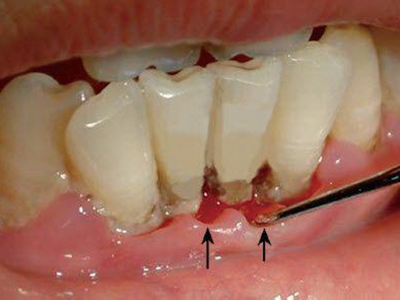

慢性龈炎的病损部位一般局限于游离龈和龈乳头,以前牙区为主,尤其以下前牙区最为显著,患者常因刷牙或咬硬物时牙龈出血而就诊。游离龈和龈乳头颜色变为鲜红或暗红色,病变较重时炎性充血可波及附着龈。龈缘变厚,龈乳头圆钝肥大,可增生呈球状,覆盖牙面。牙龈松软脆弱,缺乏弹性。

当牙龈以增生性反应为主时,龈缘和龈乳头呈坚韧的实质性肥大,质地较硬而有弹性。龈沟液量增多,还可能出现龈沟溢脓现象。

龈缘附近牙面上堆积的牙菌斑是引起慢性龈炎的始动因子,其他如牙石、食物嵌塞、不良修复体等均可促使牙菌斑积聚,引发或加重牙龈炎症。